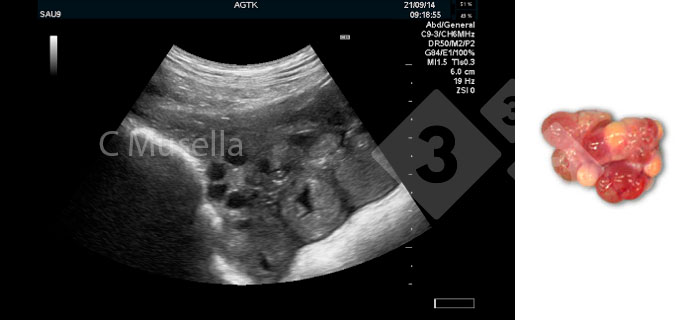

Perto da ovulação, os folículos pré-ovulatórios mudam de uma forma esférica para ovóide / poligonal. O processo ovulatório pode durar várias horas e folículos pré-ovulatórios podem ser vistos junto com corpos hemorrágicos; os últimos são claramente identificáveis por sua aparência ecogênica. A ovulação é considerada completa quando as diferentes observações sequenciais mostram o desaparecimento de todos os folículos pré-ovulatórios ou uma redução acentuada no número de folículos pré-ovulatórios observados.